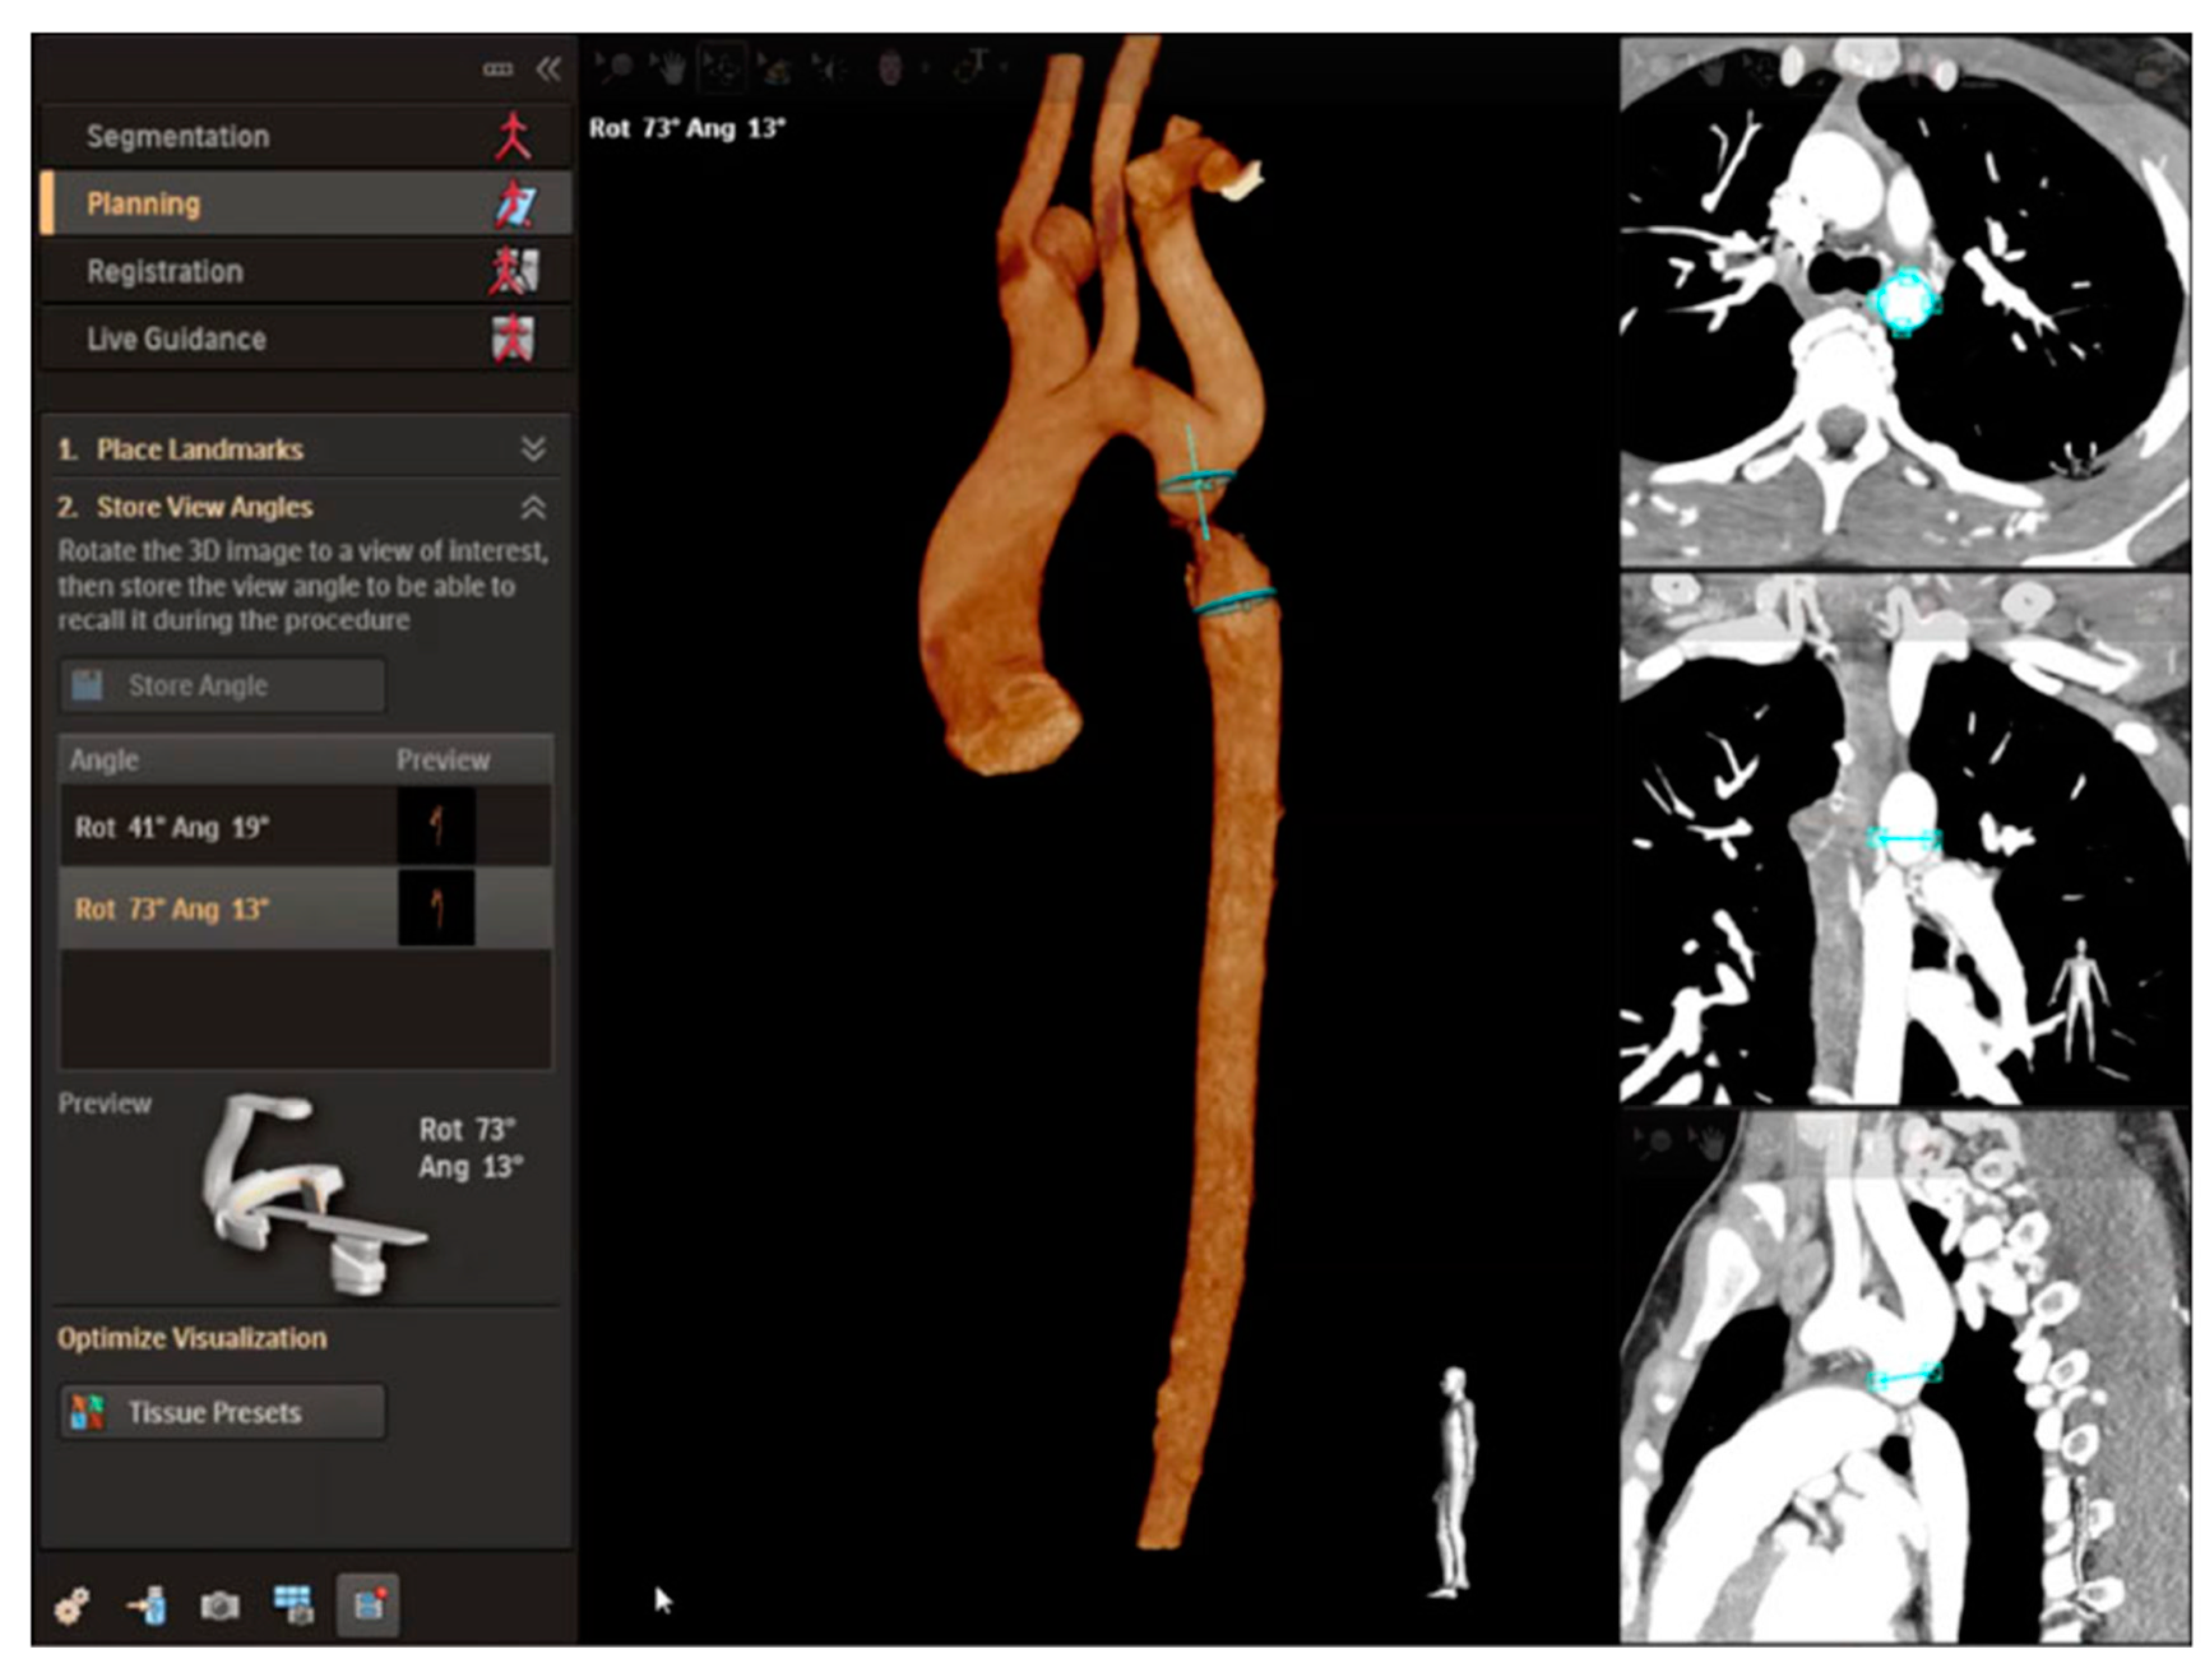

2.3. Percutaneous Pulmonary Valve Placement

2.4. Cross-Sectional Overlay Fusion in the Catheterization Lab